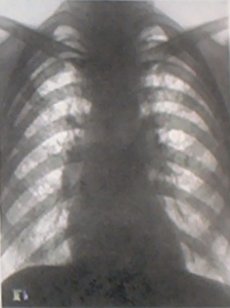

Важнейшим методом выявления силикоза была и остаётся флюорография лёгких. Однако факты свидетельствуют о том, что и не очень совершенная флюорография лёгких в 1960-х[10], и более современная в 2000-х[11], не всегда способна выявить заболевание на начальных стадиях (когда существуют наилучшие условия для сохранения жизни, здоровья и трудоспособности человека). Вскрытие 29 шахтёров, погибших во время аварии[11], и сравнение их органов дыхания с органами дыхания случайно погибших людей (не подвергавшихся воздействию пыли в шахте) показало, что при успешном прохождении медобследования (включая флюорографию) у сотрудника могли иметься изменения в лёгких, однозначно свидетельствующие о пневмокониозе. Авторы предложили дополнительные методы диагностики начальных стадий заболевания. Аналогично, вскрытие 10 случайно погибших шахтёров молибденового рудника, подвергавшихся воздействию пыли с содержанием кварца 88 % в течение 3-5 лет, показало:

- Рентгенография лёгких — 1 раз в год.